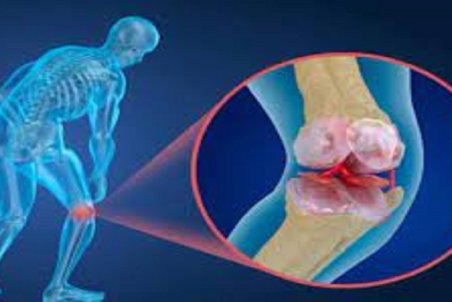

قدرت استخوانهای بدن ما را ۲ عامل اصلی تراکم استخوان و کیفیت استخوان تعیین میکند. پوکی استخوان یک بیماری عمومی استخوان است که با توده استخوانی پایین و تخریب زیرساخت بافت استخوانی و متعاقبا افزایش شکنندگی و مستعد شدن به شکستگی همراه است. تشخیص پوکی استخوان با

دردی خاموش به نام "آستئوپروز"

بیماری پوکی استخوان یا «آستئوپروز» معروف به درد خاموش، عارضهای است که در آن، تراکم سلولهای استخوانی کم و از قدرت طبیعی آن کاسته میشود و در این حالت استخوان شکننده خواهد شد و احتمال شکستگی حتی بر اثر ضربات کوچک افزایش مییابد.